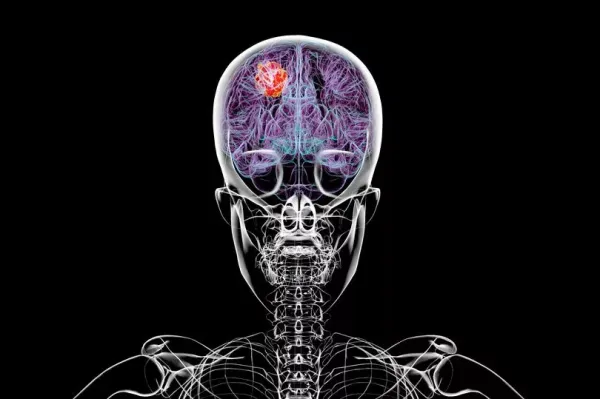

A widow is calling for the law to change to end a postcode lottery of care for brain cancer patients. Ellie James’ husband Owain died in 2024 from a type of brain tumour known as a glioblastoma. His death followed difficulties accessing personalised treatment because most of his tumour, removed during brain surgery, was not frozen.

Mrs James is heading a campaign calling for patients to have the right to have their tissue frozen and stored after surgery, enabling access to personalised treatments and genetic tests. The 36-year-old, from Caerphilly in south Wales, said this is done “inconsistently” across the NHS, creating a postcode lottery of care.

She is calling for a change in the law, dubbed Owain’s Law, which would let patients give consent about what happens to their tissue. Mrs James said she believes her husband would still be alive had the law been in place when he was receiving treatment.